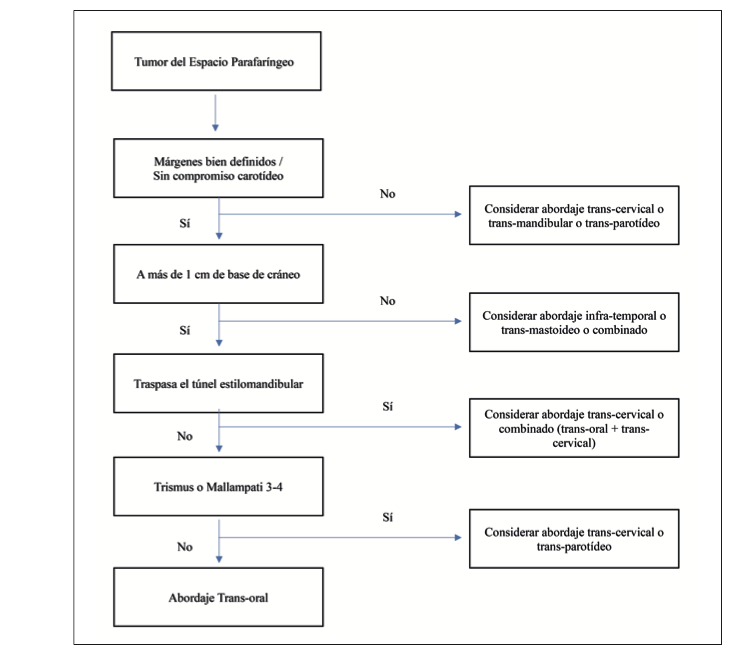

Alberto José Rojas Montejo, Angie Daniela Gutiérrez Garatejo, María Alejandra Suárez Alcázar, Alejandra Collazos Torres, Ana Yaibeth Tobio Amaya, Benigno Mendoza Ortiz

|

|